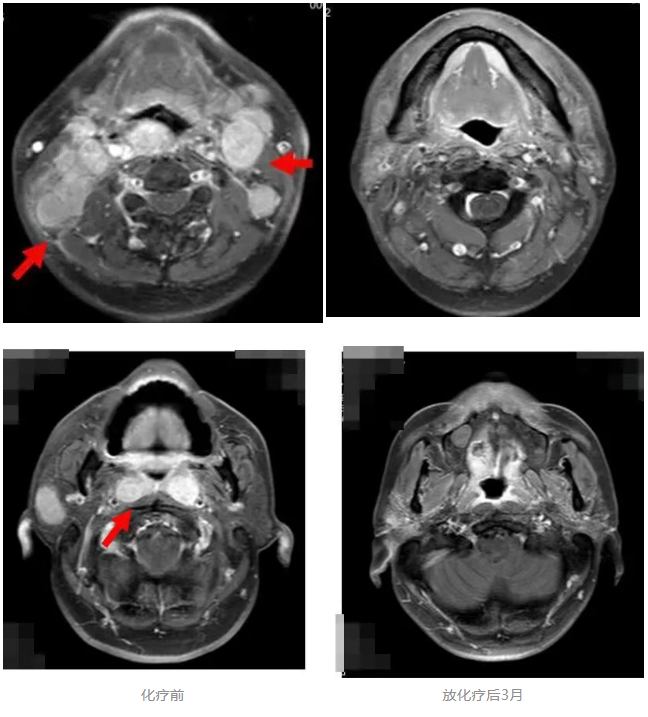

2017年4月,患者林先生(化名)确诊非角化性未分化型鼻咽癌伴双颈部及锁骨上淋巴结转移、肝转移,血EB病毒DNA载量(EB-DNA)高达176000拷贝数/ml,病情已达晚期。经TP方案全身化疗及容积旋转调强放疗(VAMT)后,EB-DNA成功清零,影像复查肿瘤基本消失。患者个人原因未行进一步维持治疗,后门诊定期复查。

2021年11月发现右鼻腔复发,行螺旋断层放疗(TOMO)配合替吉奥口服化疗。患者每次局部放疗后均实现EB-DNA转阴,进一步复查影像学病灶消退。